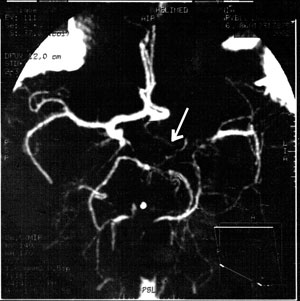

A Caucasian male was born at 38 weeks of gestation after a caesarean section, with birth weight 4000 g and birth length 57 cm, with no perinatal problems. His linear growth velocity started to decline at the age of 12 years. At the age of 14 years he started to have stabbing headaches, mainly in the left parietotemporal region, which were accompanied by nausea and hypersensitivity to light and sounds. Retractile testes had also been diagnosed since early childhood. On admittance to our Department, at the age of 154/12 years, the boy's height was 146 cm (-4.3 SDS), puberty P2G2A1 according to Tanner staging, and the testes were palpable in the inguinal canal. The deviation from mid-parental height was _3.3 SDS, and height velocity prior to admittance was estimated to be 2.8 cm/year. Other signs on physical examination were discrete facial dysmorphy, bruxism and luxation of the temporomandibular joint. An endocrine evaluation was carried out. The results of basal and stimulated hormonal assays showed low growth hormone concentrations (max 2.6 µg/L), without other pituitary hormone insufficiencies (Table 1 ). The bone age using the Greulich and Pyle standards was 116/12. In the magnetic resonance imaging (MRI) of the hypothalamic and pituitary region, a normal pituitary gland was visualised. However, in the left hemisphere there was fascicular intensification, suggesting vascular malformation. Bilateral complex flow disturbances were noted in ultrasound Doppler of the carotid arteries. These findings prompted imaging by angiocomputed tomography, which is presented in Figure 1. The decisive investigation was panangiography, in which the most abnormal vascular lesions were localised in the left hemisphere. The left internal carotid artery was narrowed with no visible C1 segment. The segment M1 of the middle cerebral artery as well as anterior cerebral arteries were absent. Collateral circulation through meningeal branches of the external carotid artery and branches of the posterior cerebral artery was visualised. This angiographic image suggested moyamoya disease.

Figure 2. Angio-computed tomography. An arrow indicates the area of interest with the invisible left carotid artery, a fragment M1 of the left middle cerebral artery, segment A2 of anterior arteries diverging from A1 segment of the right anterior artery. Collateral vessels between middle and anterior arteries on the left side.